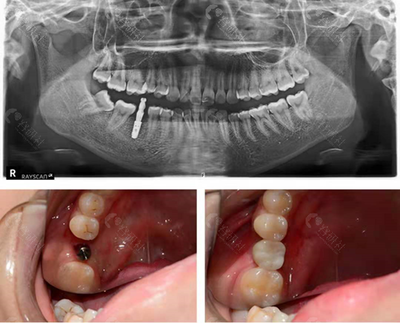

蛀牙是最常见的疾病之一。蛀牙的原因有很多,通常是不良习惯造成的,比如刷牙方法不对、没有保持良好的口腔清洁习惯、偏爱甜食等。在蛀牙初期,大多数人通常会忽视它,认为小黑点与它无关,但时间长了,蛀牙就会发展成严重的口腔问题,破坏牙齿的完整性,导致蛀牙,进而损害牙齿的中枢神经系统。蛀牙的处理:补牙拔牙:首先将病变组织从洞内取出,然后进行一系列消毒工作,最后根据洞的形状填充特殊材料。补牙步骤完成后,医生会对牙齿进行打磨。